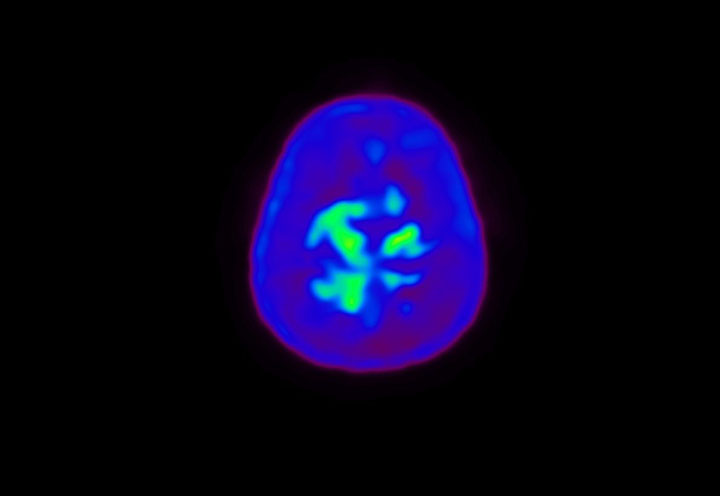

Head / Case4 : Amyloid

Courtesy : Kindai University Hospital

- Injected dose: 3.21 MBq/kg, 18F-Flutemetamol

- Uptake time: 100 minutes

- Scan time: 20 minutes